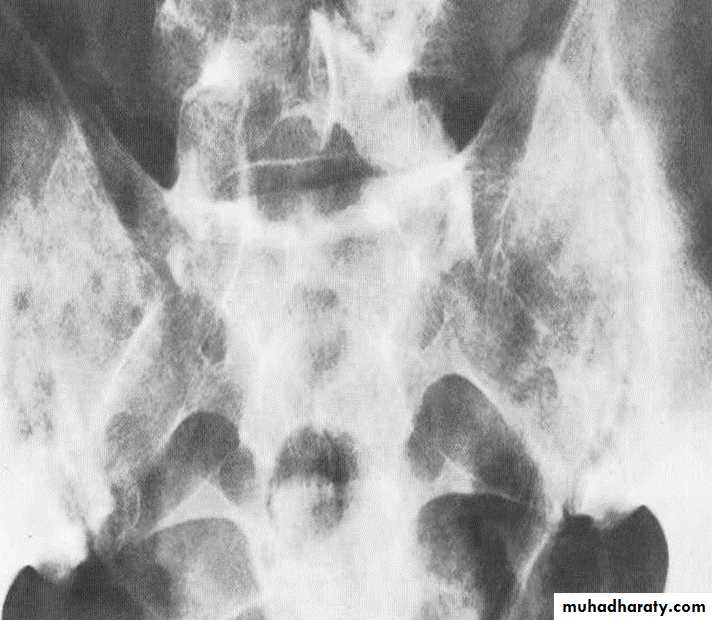

Ankylosing spondylitis-early

(A) Serrated marginsof sacroiliac joints and peri articular sclerosis.

(B) CT scanning demonstrates bilateral sacroiliitis